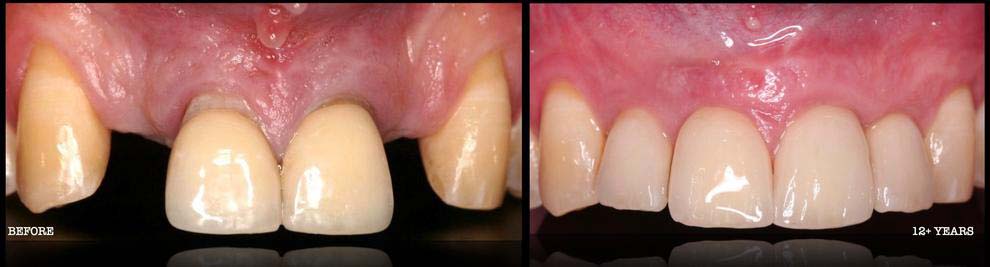

- GUM REGENERATION/GRAFTING FOR RECEDING TISSUES --> GINGIVAL RECESSION THERAPY